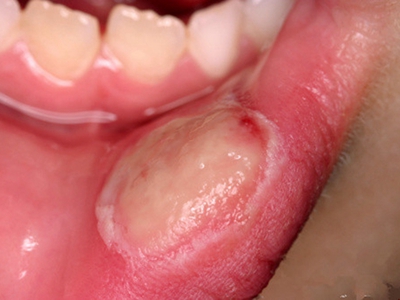

过敏性接触性口炎患者接触变应原后,经2-3天在接触部位发生病变,轻者黏膜肿胀发红,或形成红斑。重者发生水疱、糜烂或溃疡,甚至组织坏死。病变除在接触部位外,也可向邻近部位扩展。口腔科临床常见为修复材料引起的过敏性接触性口炎。

过敏性接触性口炎除了局部使用药物这一病因外,主要为充填和修复材料引起,如银汞合金、自凝塑料等。本病的发病多为Ⅳ型变态反应。